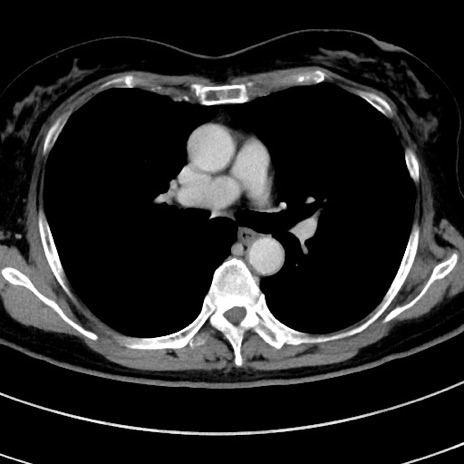

症例9(横断像)

【症例】 60歳代女性

【主訴】むかつき、みぞおちの痛み

【現病歴】3日前よりむかつきがあり、食事がとれない。

【既往歴】糖尿病

【身体所見】発熱なし、心窩部圧痛軽度あるも、腹膜刺激症状なし。

【データ】WBC 7400、CRP 1.92